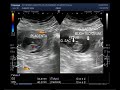

However with a blighted ovum this gestational sac appears but the embryo does not grow or develop properly. 11 Blighted ovum Misdiagnosis.

According to mayoclinic a blighted ovum is occurs when an early embryo never develops or stops developing is resorbed and leaves an empty gestational sac. The gestational sac continues to grow but the baby does not grow within the sac and is reabsorbed. My head was spinning and emotions were high all I could say was ok yes ok.

Internal Medicine 41 years experience. At about the fifth or sixth week of pregnancy an embryo should have developed and the gestational sac inside of which the fetus grows and develops is about 18 millimeters wide. A blighted ovum usually occurs within the first trimester and a womans body tends to miscarry naturally.

Cells develop to form the pregnancy sac but not the embryo itself. Also known as anembryonic pregnancy a blighted ovum happens when a fertilized egg attaches itself to the uterine wall but the embryo does not develop. He explained that with HCG levels as high as mine he should see at least the beginnings of a baby that an HCG level of 2000 is generally seen on an ultrasound.